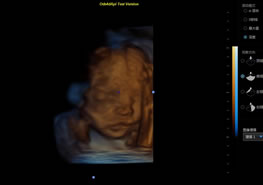

> 3D/4D成像技術(shù)/限7800選配

廣泛適用于腹部、婦產(chǎn)科、心臟、小器官、乳腺、肌骨及外周血管等諸多方面的診查,讓您在臨床超聲診斷應(yīng)用領(lǐng)域得心應(yīng)手,綻放異彩。